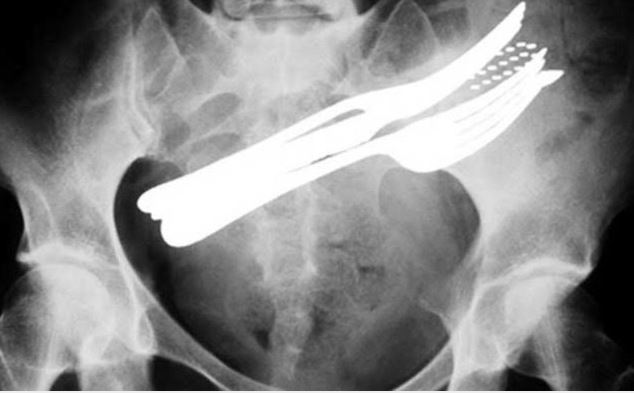

Doktorların görüp yok artık bu nasıl mümkün olur dedikleri röntgen filmleri..

Doktorluğun zor bir meslek olduğu malum. Üstelik bu mesleğin icra ederken bazı zamanlar öyle vakalar ortaya çıkmış ki, doktorlar bile anlamlandırmakta zorluk çekmişler.